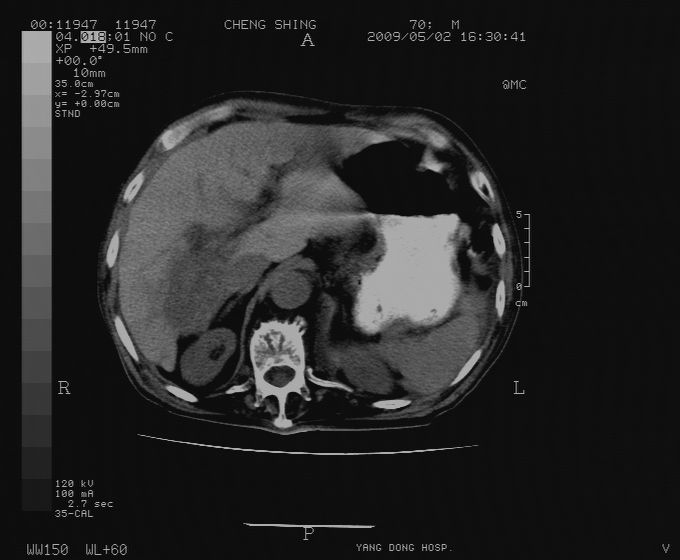

标题: CT19743:男70岁,肺部疾病入院,B超发现肝右叶占位,CT [打印本页]

标题: CT19743:男70岁,肺部疾病入院,B超发现肝右叶占位,CT

肝表面塌陷,病灶周围有子灶,前面较大子灶强化符合肝癌表现,考虑肝癌肝转移可能性大.

1.考虑肝癌肝转移

2.两侧胸水,左下肺不张!

1)考虑肝癌并肝内转移。2)少量腹水。3)双侧胸腔积液。

1)考虑肝癌并肝内转移。2)少量腹水及双侧胸腔积液。3)椎体退变。